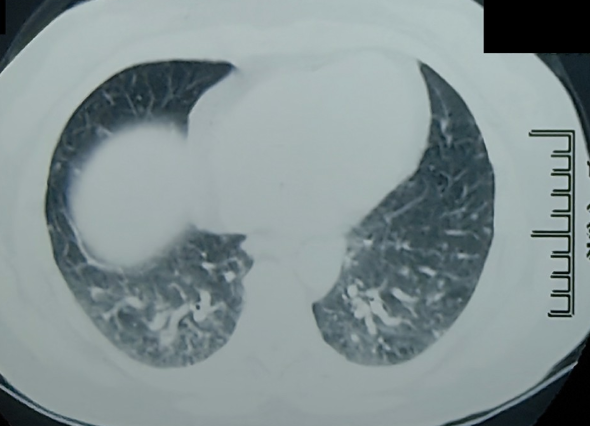

病例中的病人是一名中年妇女,她去上海交通大学医学院附属仁济医院治疗,因为“两侧耳轮肿胀疼痛伴双手关节疼痛和胸闷”。检查发现,患者两侧耳轮呈特征性硬结节样变化,并伴有明显的压痛。同时,患者两侧的掌指关节和指间关节也有压痛。进一步的胸部CT检查结果显示,患者双肺多发性结节,并伴有纵隔淋巴结肿大。但患者血清ACE水平和血钙检查结果均在正常范围内,结核相关检查均为阴性。

通过严格的分析和逐步的调查,研究小组在全面排除反复性多软骨炎、系统性血管炎、白塞氏病、肺结核感染、硅肺等疾病后,最终诊断出患者患有结节性疾病。经过激素和甲氨蝶呤的联合治疗,患者的临床表现和影像学表现得到了显著改善。